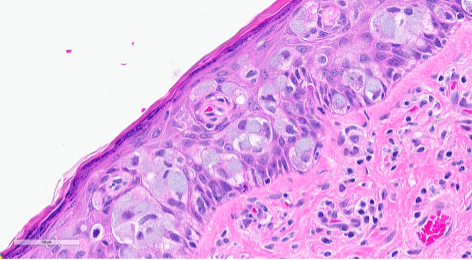

Figure 3. Section from the right vulva. In other areas of the epidermis, the same tumor cells are seen with intracytoplasmic mucin.

Primary Paget disease of the vulva is a rare in situ adenocarcinoma that arises in the labium minus or majus and most commonly affects postmenopausal women. Patients may present with itching or burning that has been present for years before undergoing a biopsy. On physical examination, the vulvar lesion is raised and may look erythematous or eczematous and can extend to the vagina and cervix. On microscopy, the tumor cells may be singly dispersed or arranged in a nested pattern. The nuclei are large and vesicular with prominent nucleoli. There is abundant pale, eosinophilic cytoplasm and intracytoplasmic mucin can be seen. The tumor is most commonly positive for CK7, GATA3, CEA, and GCDFP-15 and negative for PAX8, SOX10, and HPV ISH. This panel is helpful when differentiating it from other entities. However, there are reports of p16 and PAX8 positivity in Paget disease of the vulva, so careful interpretation of morphologic features and ancillary studies is important.

In some cases, there may be melanin pigment throughout the epidermis and dermis, which gives rise to a melanoma differential. In this situation, SOX10 and Melan-A will stain the background melanocytes; however, the Paget tumor cells will be negative. Other differentials include vulvar intraepithelial neoplasia, HPV-independent (dVIN), high-grade squamous intraepithelial lesion (HSIL) with pagetoid spread, and secondary Paget disease. dVIN can microscopically look like Paget with the nested, pale tumor cells, as well as mucinous differentiation, however, it will be negative for CK7 and GCDFP-15. HSIL can mimic Paget with mucinous areas, melanin pigment, and pagetoid spread too. To best differentiate HSIL from Paget, high-risk HPV ISH is useful, as it will be positive in HSIL and negative in Paget. The last differential is secondary Paget, which is much less common and originates in another location before metastasizing, such as the rectum, cervix, or bladder. These would stain for CDX2, CK20, or uroplakin-3, respectively.